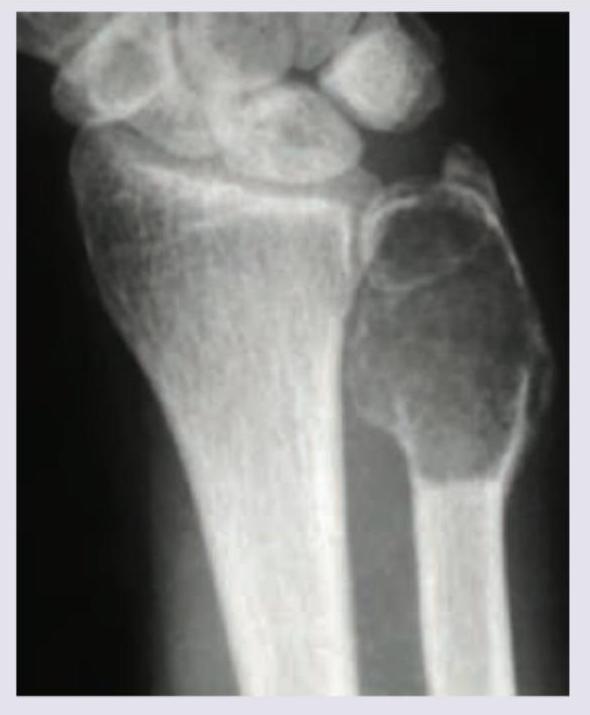

99. A 20-year-old male patient presents with a lesion in the wrist joint. The X-ray appearance is given below. What is the likely diagnosis?

Explanation: ***Simple bone cyst*** - The X-ray image shows a **lucent, well-defined lesion** in the diaphysis/metaphysis of the ulna, often seen in the proximal humerus or femur, but can occur in other long bones. - The lesion has a **thin, sclerotic rim** without significant periosteal reaction or cortical destruction, suggesting a benign, fluid-filled lesion like a simple bone cyst. *Osteoclastoma* - This typically presents as an **eccentric, expansile lytic lesion** in the epiphysis or metaphysis of long bones, often with a "soap bubble" appearance. - It usually occurs near the **knee or distal radius** but the lesion in the image lacks the characteristic aggressive features and epiphyseal involvement of osteoclastoma. *Adamantinoma* - This is a rare, malignant bone tumor that almost exclusively occurs in the **tibia**. - It presents as a **lytic, often multifocal lesion** with central sclerosis or cystic changes, which does not match the appearance or location of the lesion in the ulna. *Multiple myeloma* - This is a systemic malignancy causing **punched-out lytic lesions** in the axial skeleton (skull, spine, pelvis) and proximal long bones. - The appearance in the image is of a single, well-defined cyst, not the widespread, multiple lucencies typical of multiple myeloma.